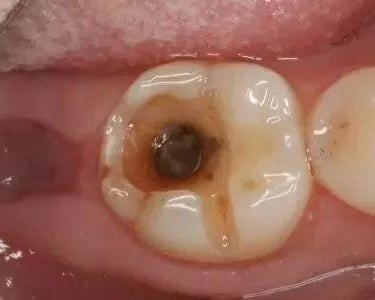

Pulpitis Crónica Hiperplásica

La pulpitis crónica hiperplásica es una inflamación de la pulpa con crecimiento excesivo de tejido pulpar a través de una caries abierta.

Los pacientes notan un tejido rojo que sobresale de la cavidad dental.

El tratamiento incluye la eliminación del tejido afectado y un tratamiento de conducto. Es crucial tratar la caries para evitar infecciones adicionales.